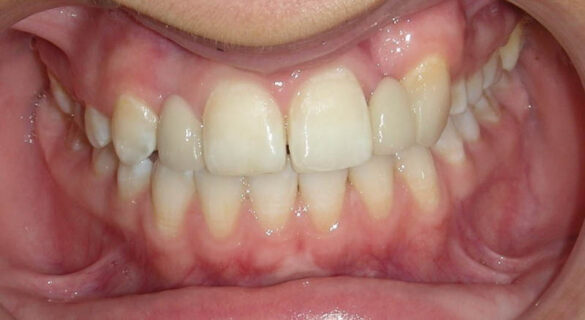

În aprilie 2009, după 37 luni de tratament, au fost îndepărtate aparatele fixe (fig. 6). Pentru contenţie, s-a aplicat un retainer fix colat pe faţa linguală a celor şase dinţi frontali inferiori şi o placă palatinală Hawley care încorporează dinţi acrilici în dreptul incisivilor laterali pentru a menţine un aspect estetic până când medicul protetician va putea realiza punţile dentare. În plus, s-a utilizat un arc vestibular care să consolideze contenţia şi care să permită aplicarea unor forţe uşoare, cu direcţie linguală, dacă este necesar.25 Croşetele ”în deget” sunt situate distal de incisivii centrali maxilari şi mezial de caninii superiori, pentru a permite o deplasare discretă mezio-distală a dinţilor, dacă este necesar (fig. 7).Înainte de îndepărtarea aparatului, a fost consultat medicul protetician. S-a pus problema dacă pacienta ar avea dificultatea de a purta pe termen lung un aparat mobil de contenţie, din cauza dificultăţilor de respiraţie şi a tusei, asociate cu fibroza chistică. În plus, din cauza anodonţiei de incisivi laterali superiori, osul alveolar este dezvoltat insuficient şi prezintă, astfel, dimensiuni prea reduse pentru inserarea implantelor dentare; procedura de augmentare a ţesuturilor moi şi dure ale crestei alveolare ar fi inevitabilă. Vârsta pacientei şi creşterea şi dezvoltarea corespunzătoare au fost, de asemenea, luate în considerare.19 Ortopantomograma finală relevă anodonţia molarilor de minte inferiori şi a celui superior drept pe lângă anodonţia incisivilor laterali maxilari şi a premolarului secund drept inferior. De asemenea, se remarcă aplatizarea rădăcinilor incisivilor centrali maxilari, care era prezentă şi pe radiografia efectuată înainte de tratament (fig.8).

Când pacienta s-a prezentat la control câteva săptămâni mai târziu, s-a observat apariţia unei diasteme de 0,5mm (fig. 13, 14). Medicul protetician a reechilibrat feţele palatinale ale restaurărilor şi ale dinţilor stâlpi, iar medicul ortodont a aplicat o placă Hawley de contenţie, ce prezintă un arc vestibular în contact cu feţele vestibulare ale tuturor dinţilor. S-a îndepărtat din acrilat în dreptul feţelor linguale ale incisivilor centrali, iar arcul a fost activat la nivelul incisivilor centrali astfel încât să exercite asupra acestora forţe uşoare direcţionate în sens lingual (fig. 15). Diastema a putut fi închisă cu ajutorul plăcii Hawley, iar ulterior medicul protetician a aplicat, printr-o metodă conservatoare, un retainer fix, colat intracoronal între porţiunile meziale vecine ale feţelor palatinale ale incisivilor centrali superiori. A fost fixat un ştift de aur cu ajutorul unei răşini compozite, menţinând placa Hawley în cavitatea orală, pentru a nu-i compromite stabilitatea. Ulterior, toate contactele de la nivelul incisivilor centrali, înregistrate în poziţii centrice şi în mişcări de lateralitate şi de propulsie, au diminuate până au devenit slabe. Pacienta şi-a exprimat dorinţa ca ambrazura incizală să fie mai redusă, aşa încât aceasta a fost închisă parţial cu ajutorul suprafeţei vestibulare a retainerului fix (fig. 16, 17). Pacienta şi părinţii au fost mulţumiti de rezultatul final obţinut.